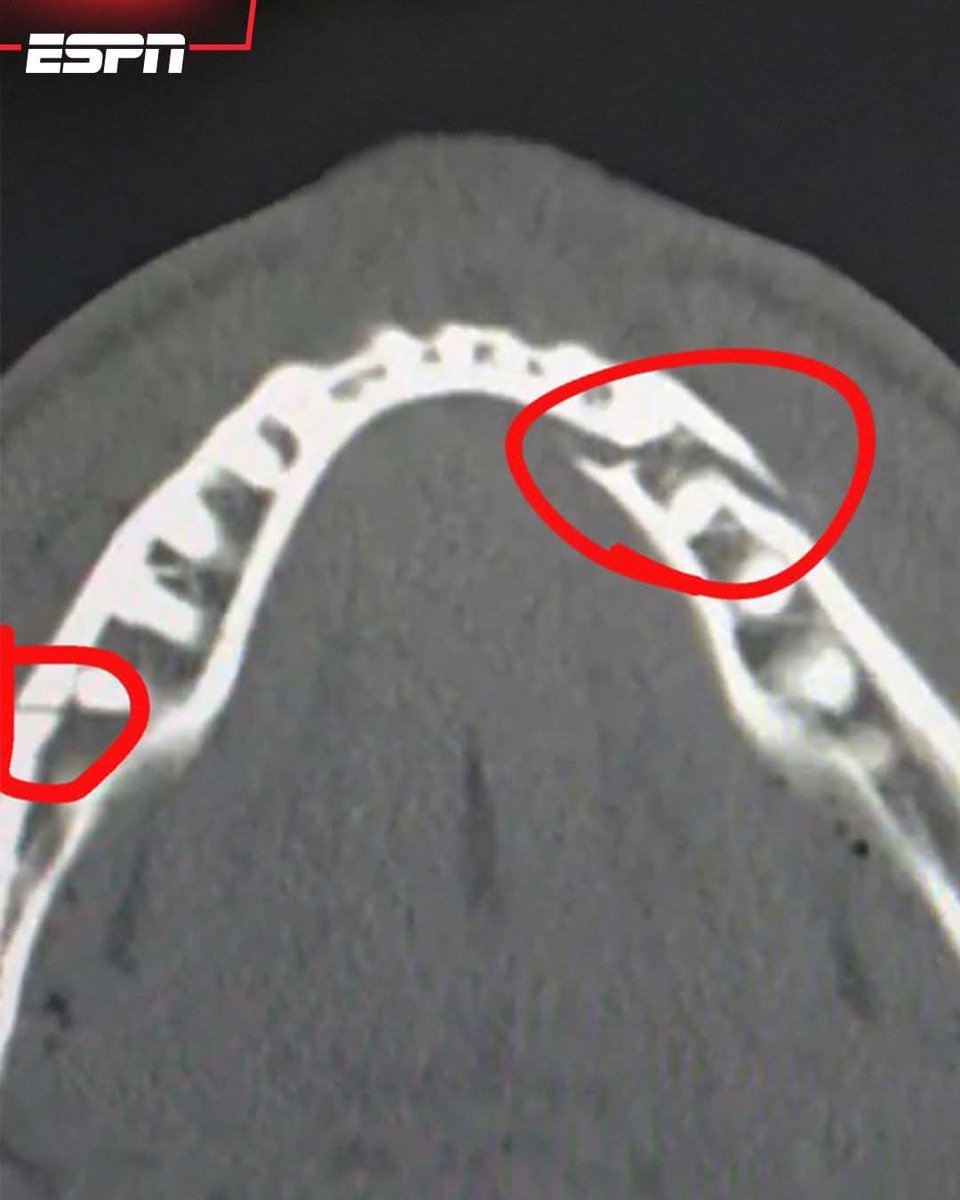

- JAKE PAUL CONFIRMS DOUBLE BROKEN JAW IN KO LOSS W/ ANTHONY JOSHUA ! ๐Ÿ’ฅ ๐ŸฅŠ - ALIEN INVASION IN THE @OthersideMeta Source: @espn LIVE ๐Ÿ”ด ๐Ÿ‘‡